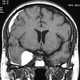

Subdural hematoma

A subdural hematoma (SDH) is a type of bleeding in which a collection of blood—usually associated with a traumatic brain injury—gathers between the inner layer of the dura mater and the arachnoid mater of the meninges surrounding the brain. It usually results from tears in bridging veins that cross the subdural space. [Source: Wikipedia ]